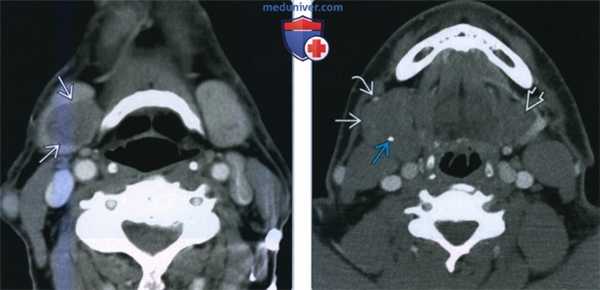

(Слева) КТ с КУ, аксиальная проекция. Локальное образование низкой плотности, происходящее из правой поднижнечелюстной железы. Образование имеет четкие контуры, что говорит о его доброкачественной природе. Для точного подтверждения диагноза требуется биопсия.

(Справа) КТ с КУ. По сравнению с левой железой, правая значительно увеличена в размерах. Смещение передней лицевой вены В говорит в пользу внутрижелезистого расположения опухоли. Из-за изоденсной структуры доброкачественная смешанная опухоль была практически не видна: подозрительными были асимметрия желез и наличие кальцификатов.